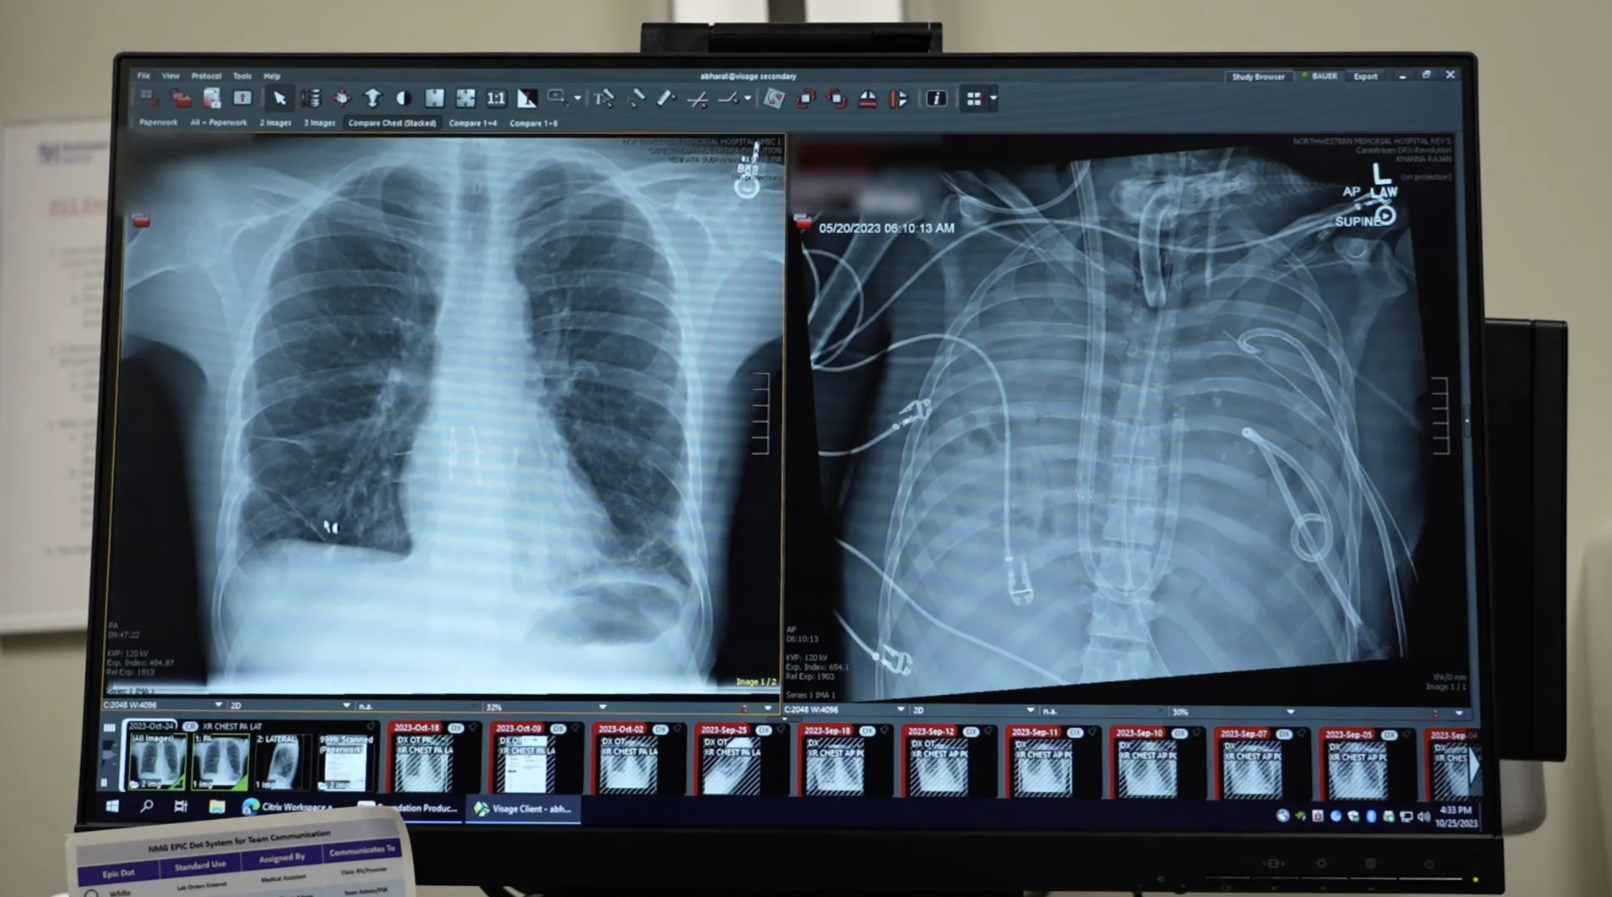

A férfi új (balra) és régi (jobbra) tüdeje

Forrás: Northwestern Medicine